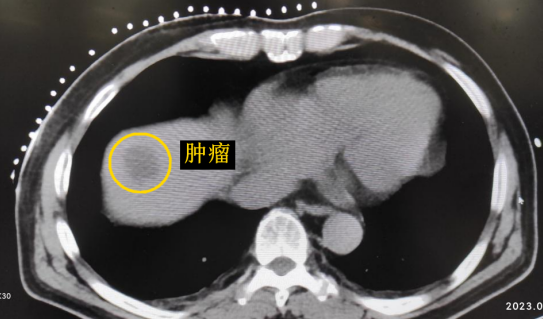

患者老年男性,曾于2021年行結(jié)腸癌手術(shù)。幾月前,發(fā)現(xiàn)肝臟轉(zhuǎn)移瘤,但沒有干預。近期CT顯示該轉(zhuǎn)移瘤明顯增大,并發(fā)現(xiàn)另一處轉(zhuǎn)移灶。

影像診療科陳寶瑩主任團隊評估后指出,較大的腫瘤位于肝頂部緊貼膈肌,如果繼續(xù)發(fā)展,腫瘤很可能突破肝包膜侵犯到膈肌,建議及時干預。病變緊臨膈肌,如果要完全消融,膈肌損傷的可能性就比較大,與其他局部治療方式比較,冷凍消融對周圍臟器、血管及神經(jīng)損傷的可能性較小、安全性更高、患者疼痛感較輕,建議通過CT精準引導下經(jīng)皮微創(chuàng)冷凍消融治療。

CT精準定位腫瘤